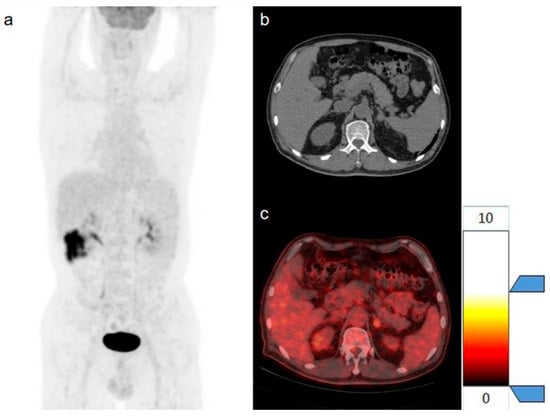

2.5. Three-Dimensional Segmentation